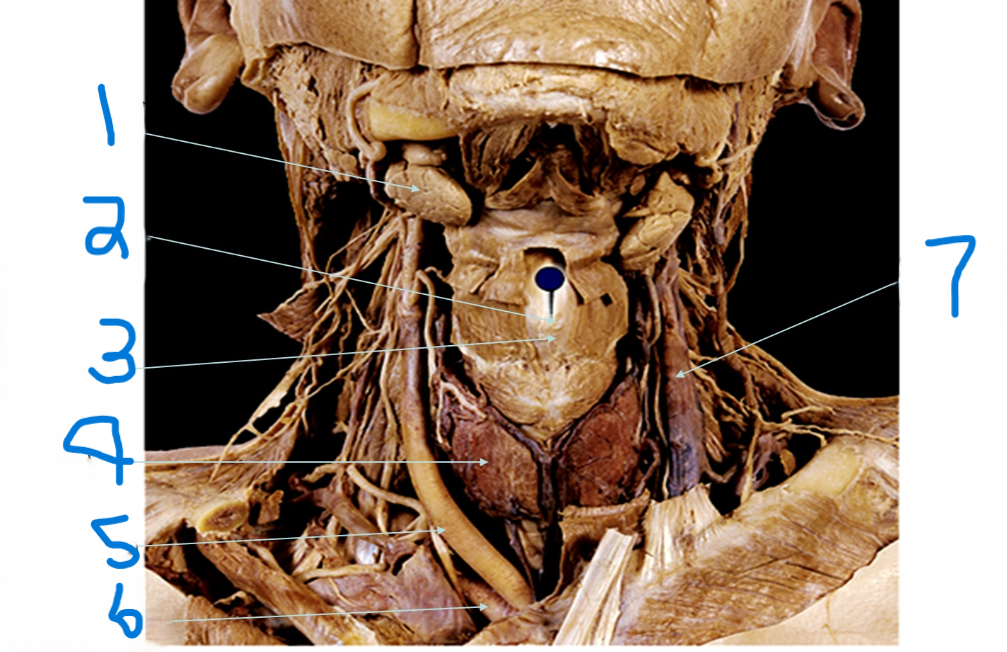

What is depicted by #1

Laryngeal Prominence (adams apple)

What is depicted by #2

Thyroid cartilage

What is depicted by #3

Thyroid gland

What is depicted by #4

Right common carotid artery

What is depicted by #5

Right subclavia artery

What is depicted by #6

Left internal jugular vein

What is depicted by #7